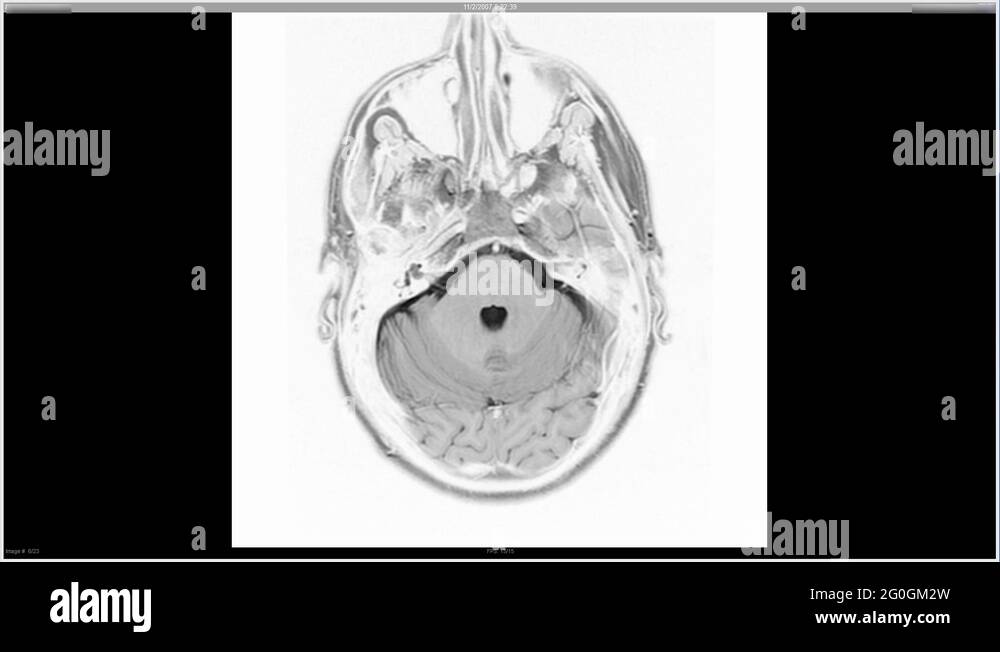

Alzheimer's X Ray . Doctors frequently request a ct or mri scan of the brain when they are examining a patient with suspected dementia. Medial temporal lobe atrophy on mri differentiates alzheimer’s disease from dementia with lewy. A head ct can show shrinkage of brain. Medial temporal lobe atrophy on mri differentiates alzheimer’s disease from dementia with lewy bodies and vascular cognitive impairment: To rule out other possible causes of your symptoms and look for possible signs of damage caused by alzheimer's disease, your specialist may. Ct scans are the most common type of brain scan used in. Areas that are black and blue represent. The scans show a healthy brain, a brain with mild cognitive impairment and a brain with alzheimer's disease.

A head ct can show shrinkage of brain. Medial temporal lobe atrophy on mri differentiates alzheimer’s disease from dementia with lewy. Doctors frequently request a ct or mri scan of the brain when they are examining a patient with suspected dementia. Areas that are black and blue represent. To rule out other possible causes of your symptoms and look for possible signs of damage caused by alzheimer's disease, your specialist may. The scans show a healthy brain, a brain with mild cognitive impairment and a brain with alzheimer's disease. Medial temporal lobe atrophy on mri differentiates alzheimer’s disease from dementia with lewy bodies and vascular cognitive impairment: Ct scans are the most common type of brain scan used in.

Alzheimer's X Ray Areas that are black and blue represent. Medial temporal lobe atrophy on mri differentiates alzheimer’s disease from dementia with lewy bodies and vascular cognitive impairment: The scans show a healthy brain, a brain with mild cognitive impairment and a brain with alzheimer's disease. Medial temporal lobe atrophy on mri differentiates alzheimer’s disease from dementia with lewy. Doctors frequently request a ct or mri scan of the brain when they are examining a patient with suspected dementia. To rule out other possible causes of your symptoms and look for possible signs of damage caused by alzheimer's disease, your specialist may. A head ct can show shrinkage of brain. Areas that are black and blue represent. Ct scans are the most common type of brain scan used in.